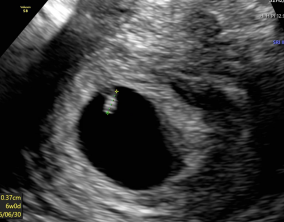

포기 직전, 원인을 찾고 만난 생명

전문적이고 섬세한 진료로 정확한 원인을 짚어주시는 이유정 원장님 덕분에 저희 부부에게 다시 희망이 생겼습니다. 주사실 선생님들도 너무 친절하시고 전문성이 높아서 시술 과…

자궁각임신의 아픔을 지나 찾아온 기적

직장인을 위한 진료 시간이 있어 꾸준히 치료를 받기 좋았고, 이경훈 원장님은 늘 젠틀하고 상황을 명확하게 판단해주셔서 신뢰가 갔어요. 간호사 선생님들도 가족처럼 따뜻해서…